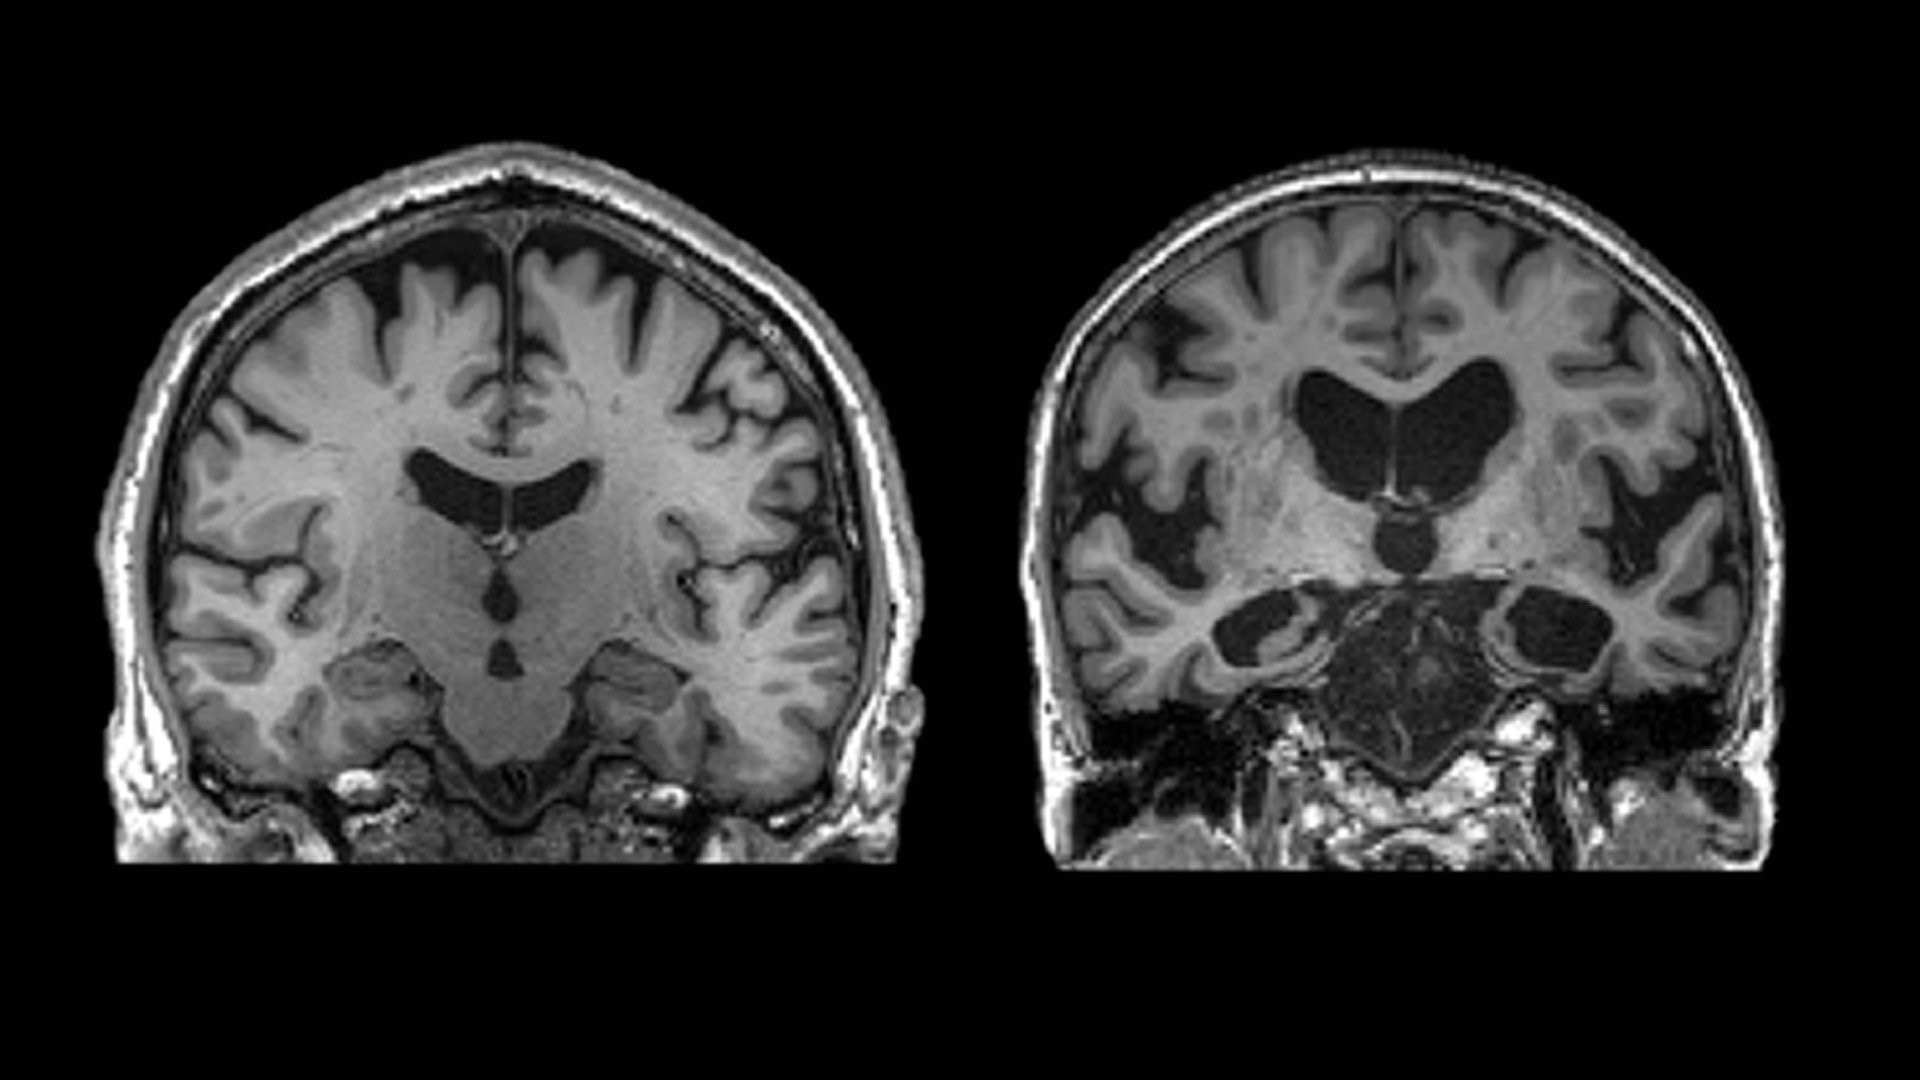

중년을 어떻게 보내느냐에 따라 당신의 뇌는 치매에 부쩍 다가설 수도 있고, 한없이 미룰 수도 있다. 치매 관리의 핵심 시기는 중년이다. 부피가 충분해 보이는 왼쪽 뇌는 정상인. 쪼그라들어 휑해 보이는 오른쪽 뇌는 알츠하이머 환자. 사진 Leonidas Chouliaras et al., 2023

최근 중년의 잠재력에 과학자들이 주목하고 있다. 중년이 뇌 건강의 갈림길이자 전환기라는 사실이 밝혀지면서다. 우리는 일생 똑같은 속도로 늙어간다고 생각하지만, 중년에 접어들면 개인차가 극심해진다. 누군가는 짧은 중년 뒤 바로 노년에 진입하고 노쇠의 징후를 보인다. 하지만 다른 이는 중년 시기에 노화 속도를 최소화하고 활력 넘치는 노년을 즐긴다.

중년에 접어들면 대뇌 백질과 해마의 퇴화가 시작된다. 백질은 우리 뇌의 네트워크를 이뤄 복잡한 작업을 수행하게 해주는 부위다. 해마는 기억, 감정, 학습을 담당하며 우리의 정체성을 이루는 핵심 부위다.